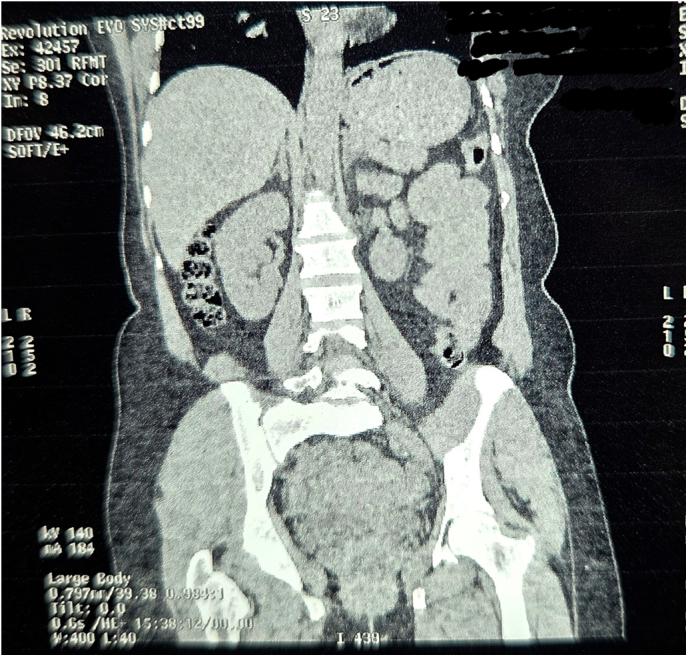

A 55-year-old woman presented with signs of small bowel obstruction. Imaging(Fig. 1-11) revealed ileo-ileal intussusception. Intraoperatively(Fig. 16-18), a Double intussusception configuration was observed where one intussuscepted segment acted as the lead point for a second. A firm lesion at the apex was resected. Histopathology confirmed Inflammatory Pseudotumor(Fig. 12-15). The patient recovered uneventfully and remained asymptomatic at 6-month follow-up.

一名55岁女性出现小肠梗阻症状。影像学检查(图1 - 11)显示回肠 - 回肠套叠。术中(图16 - 18)观察到双重肠套叠结构,其中一个套入段作为第二个套入段的引导点。切除顶端的一个坚实病变。组织病理学证实为炎性假瘤(图12 - 15)。患者恢复顺利,6个月随访时无症状。